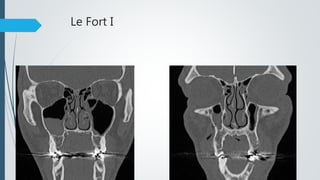

Facial bone (Le Fort) fractures

(Midface)

 involve separation of all or a portion of the midface from the skull base

 the pterygoid plates of the sphenoid bone need to be involved as these

connect the midface to the sphenoid bone dorsally.

3types

 Le Fort I

 Horizontal fracture through the maxilla that involves the piriform aperture.

 Le Fort II

 Pyramidal fracture that involves the nasofrontal junction, infraorbital rims,

medial orbital walls, orbital floors and the zygomaticomaxillary suture lines.

 Le Fort III

 Craniofacial separation

 Consists of nasofrontal junction fractures that extend laterally

through the orbital walls and zygomatic arches.

Le Fort I – Floating palate

Le Fort II – Floating maxilla

Le Fort III – Floating face

Le Fort I